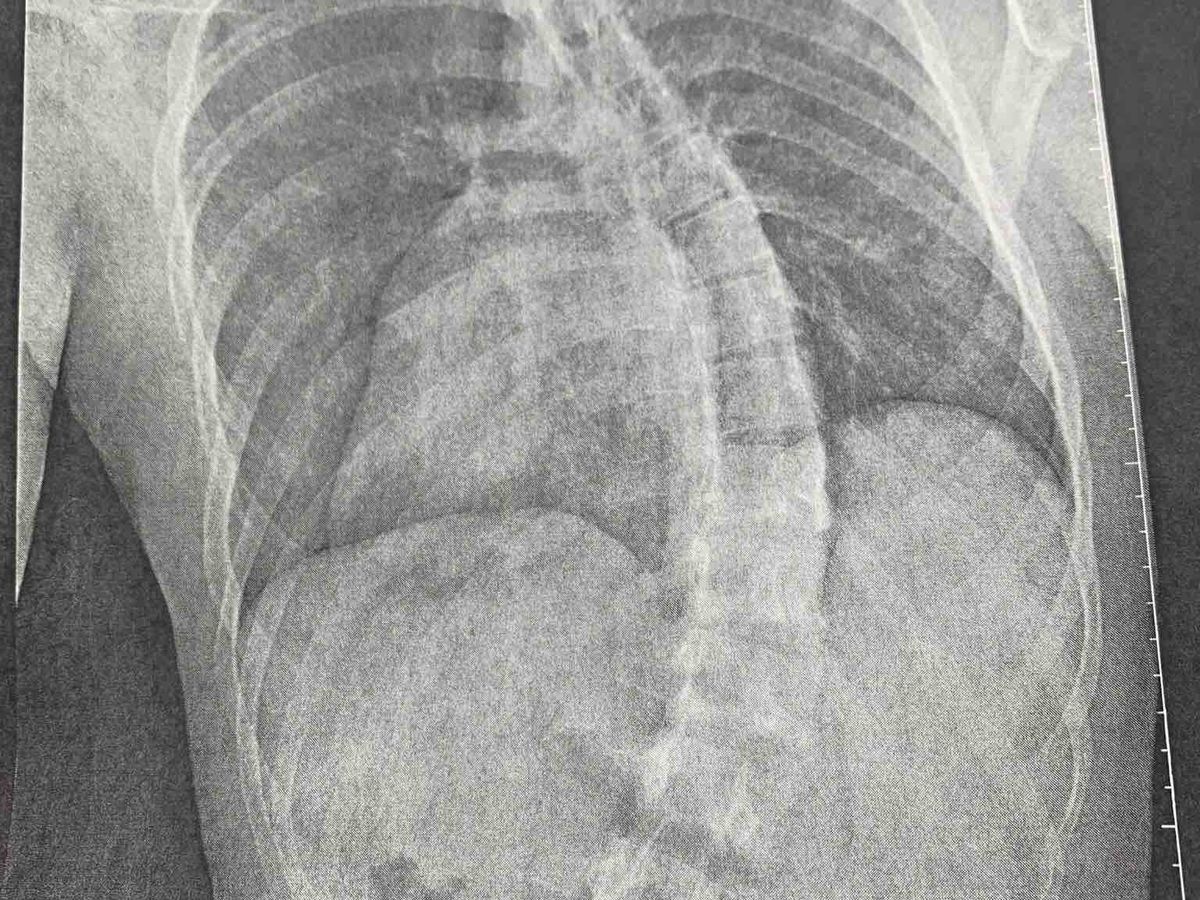

Update 1/9/20: This is what scoliosis looks like on an 18yr old body. The picture does nothing to describe the pain Caleb experiences 24/7 but you’d never know it by visiting with him or watching him go about his job at American Eagle. His love of God, Church and Family is so evident in his life. I’d like to take this time to thank those who have donated on GoFundMe and those who have helped in other ways; such as Caleb’s Uncle & Aunt who paid for the hotel rooms, his Aunt & Uncle who have donated money towards the MRI using their HSA account. Not everyone is comfortable donating thru GoFundMe and I thoroughly understand that. We appreciate any and every thing you do to help. Keep those prayers coming. Love y’all! Our 18 year old grandson Caleb Yogi, will be undergoing surgery to correct severe scoliosis. Caleb was diagnosed in 2014 with a 37° “C” curve and had to wear a scoliosis brace 20 hours a day for 4 years in hopes of preventing the curve from worsening. Over the years of wearing the brace, the curve gradually got worse and he is in constant pain due to the curvature of his spine. He was seen by his specialist and informed the curve is progressively getting worse and surgery is inevitable. The surgery is scheduled February 3, 2020 at Texas Children’s in Houston. This account is created to cover cost of deductible, meals, travel and any unforeseen expenses. We greatly appreciate any donations! Please put Caleb and family in your prayers as this will be a lengthy process, rehab and recovery.